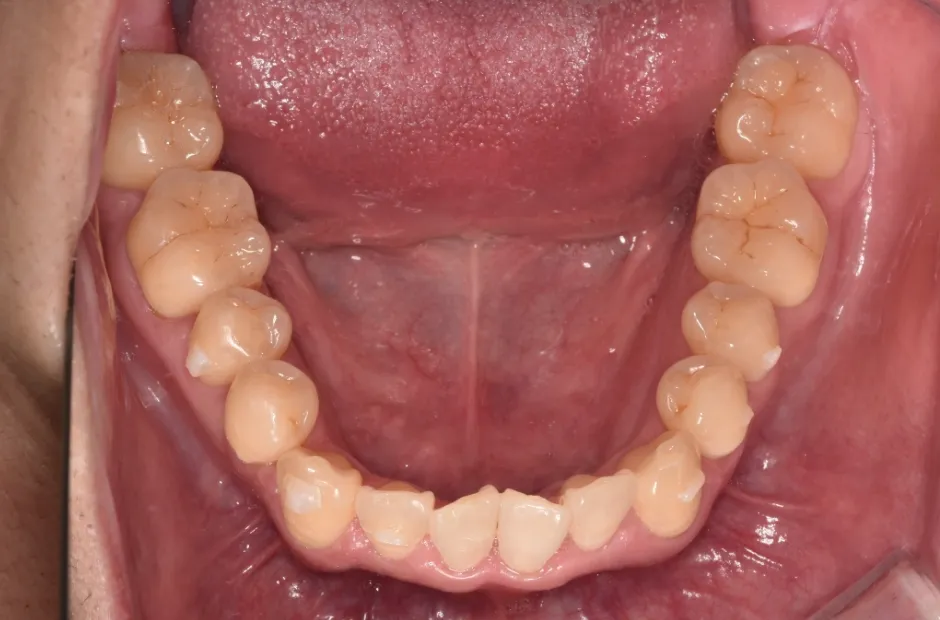

叢生

| 診断名・主訴 | 叢生 |

|---|---|

| 年齢・性別 | 43歳・女性 |

| 治療期間・回数 | 2年7か月 27回 |

| 治療に用いた主な装置 | 舌側矯正 |

| 抜歯部位 | 両顎4,4 |

| 治療費 | 100万円(税抜) |

| リスク・副作用 | 装置による違和感・疼痛・歯肉退縮・歯根吸収・虫歯のリスクなど |

治療後